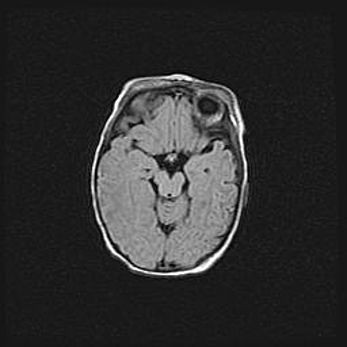

Лейкомаляция с кистозно-глиозной дегенерацией головного мозга.

Возраст: 2 месяца 25 дней

Вес: 6400 г

Окружность головы: 40 см

Срок гестации: 41 неделя

Лейкомаляцию относят к ишемически-гипоксическим повреждениям головного мозга, диагностируемым у новорожденных. При лейкомаляции в головном мозге обнаруживают очаги некроза, возникшие после тяжелой гипоксии и нарушения кровотока. В процессе морфогенеза очаги проходят три стадии: 1) развития некроза, 2) резорбции и 3) формирования глиозного рубца или кисты. Перивентрикулярная лейкомаляция (ПЛ) встречается примерно в 12% случаев среди новорожденных, обычно – у недоношенных детей, причем, частота ее зависит от массы, с которой младенец появился на свет. Наибольшее число малышей страдает лейкомаляцией, если масса при рождении 1500-2500 г.